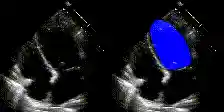

We show examples of our semantic segmentation for nine distinct patients below. Three patients have normal cardiac function, three have low ejection fractions, and three have arrhythmia. No human tracings for these patients were used by EchoNet-Dynamic.

| Normal | Low Ejection Fraction | Arrhythmia |